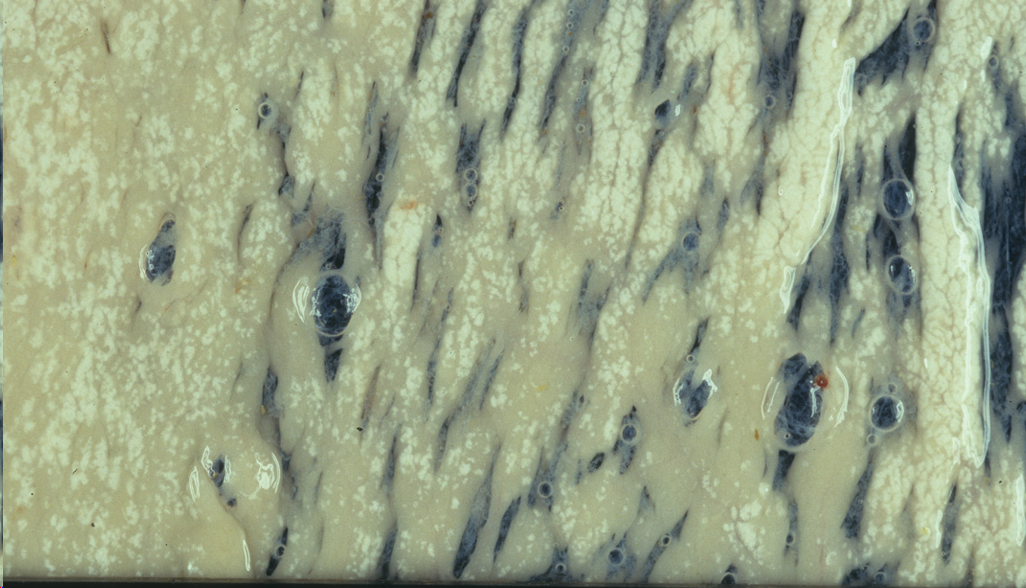

Melanosis maculosa congenita

Mas información: Melanosis maculosa congenita por cumulo de melanina, no es una enfermedad, es comestible